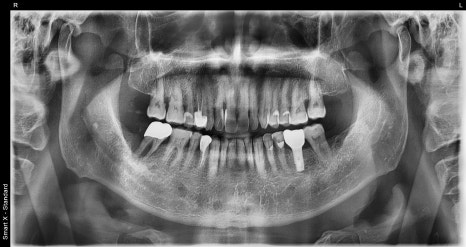

The image on the left is a panoramic X-ray taken at the initial visit, and the image on the right is an intraoral photo of the patient.

The lower right molar (#47) showed significant bone loss around the gum on the X-ray, and the tooth was very loose, so we were planning #47 extraction and implant treatment along with full gum treatment.